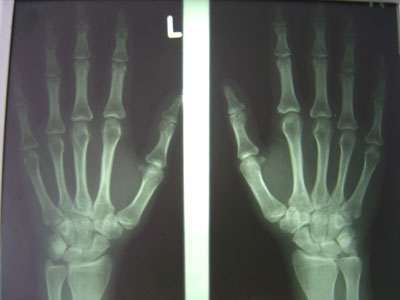

Eine 34-jährige Frau kommt in Ihre Sprechstunde mit  folgenden seit über 8 Wochen andauernden Beschwerden: Aus guter Gesundheit heraus Beginn mit Schmerzen in der rechten Schulter, im Verlauf wandernde Schmerzen in der linken Schulter, in beiden Handgelenken und mehreren MCP-Gelenken. Deutliche Morgensteifigkeit  bis zu 2 Stunden Dauer.

Im Status ist das Gänsslen Zeichen der rechten Hand positiv und an den MCP III-Gelenken ist beidseits eine diskrete Synovitis vorhanden.

Das Handröntgenbild zeigt folgenden Befund:

Hände dorsopalmar bds.

Wie interpretieren Sie diese Röntgenaufnahme?